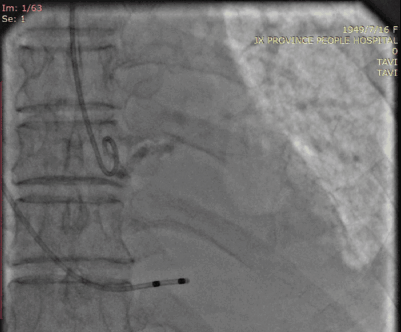

入路情况较为特殊,右股入路扭曲,左股尚可,腹主迂曲,上大鞘和过输送器时应轻柔,以防止血管并发症。决定左股作为主入路,左桡作为辅路。弓部呈锐角,过弓时应注意血管损伤,必要时借助抓捕器。

5月19日,朱奶奶被送入介入室行经导管主动脉瓣置换术,由于下肢血管入路极度扭曲,并且低血压,难以耐受长时间麻醉及手术,洪浪院长团队简化方式建立入路,再进行全麻,并迅速完成垮瓣、球囊扩张及Venus A 26mm瓣膜释放,术后造影提示瓣膜位置良好,无瓣周漏,左心室与主动脉压差从术前139mmHg降至7mmHg,手术非常成功。从病人上台至股动脉缝合共耗时100分钟,术后转入CCU进行复苏,继续监测生命体征。